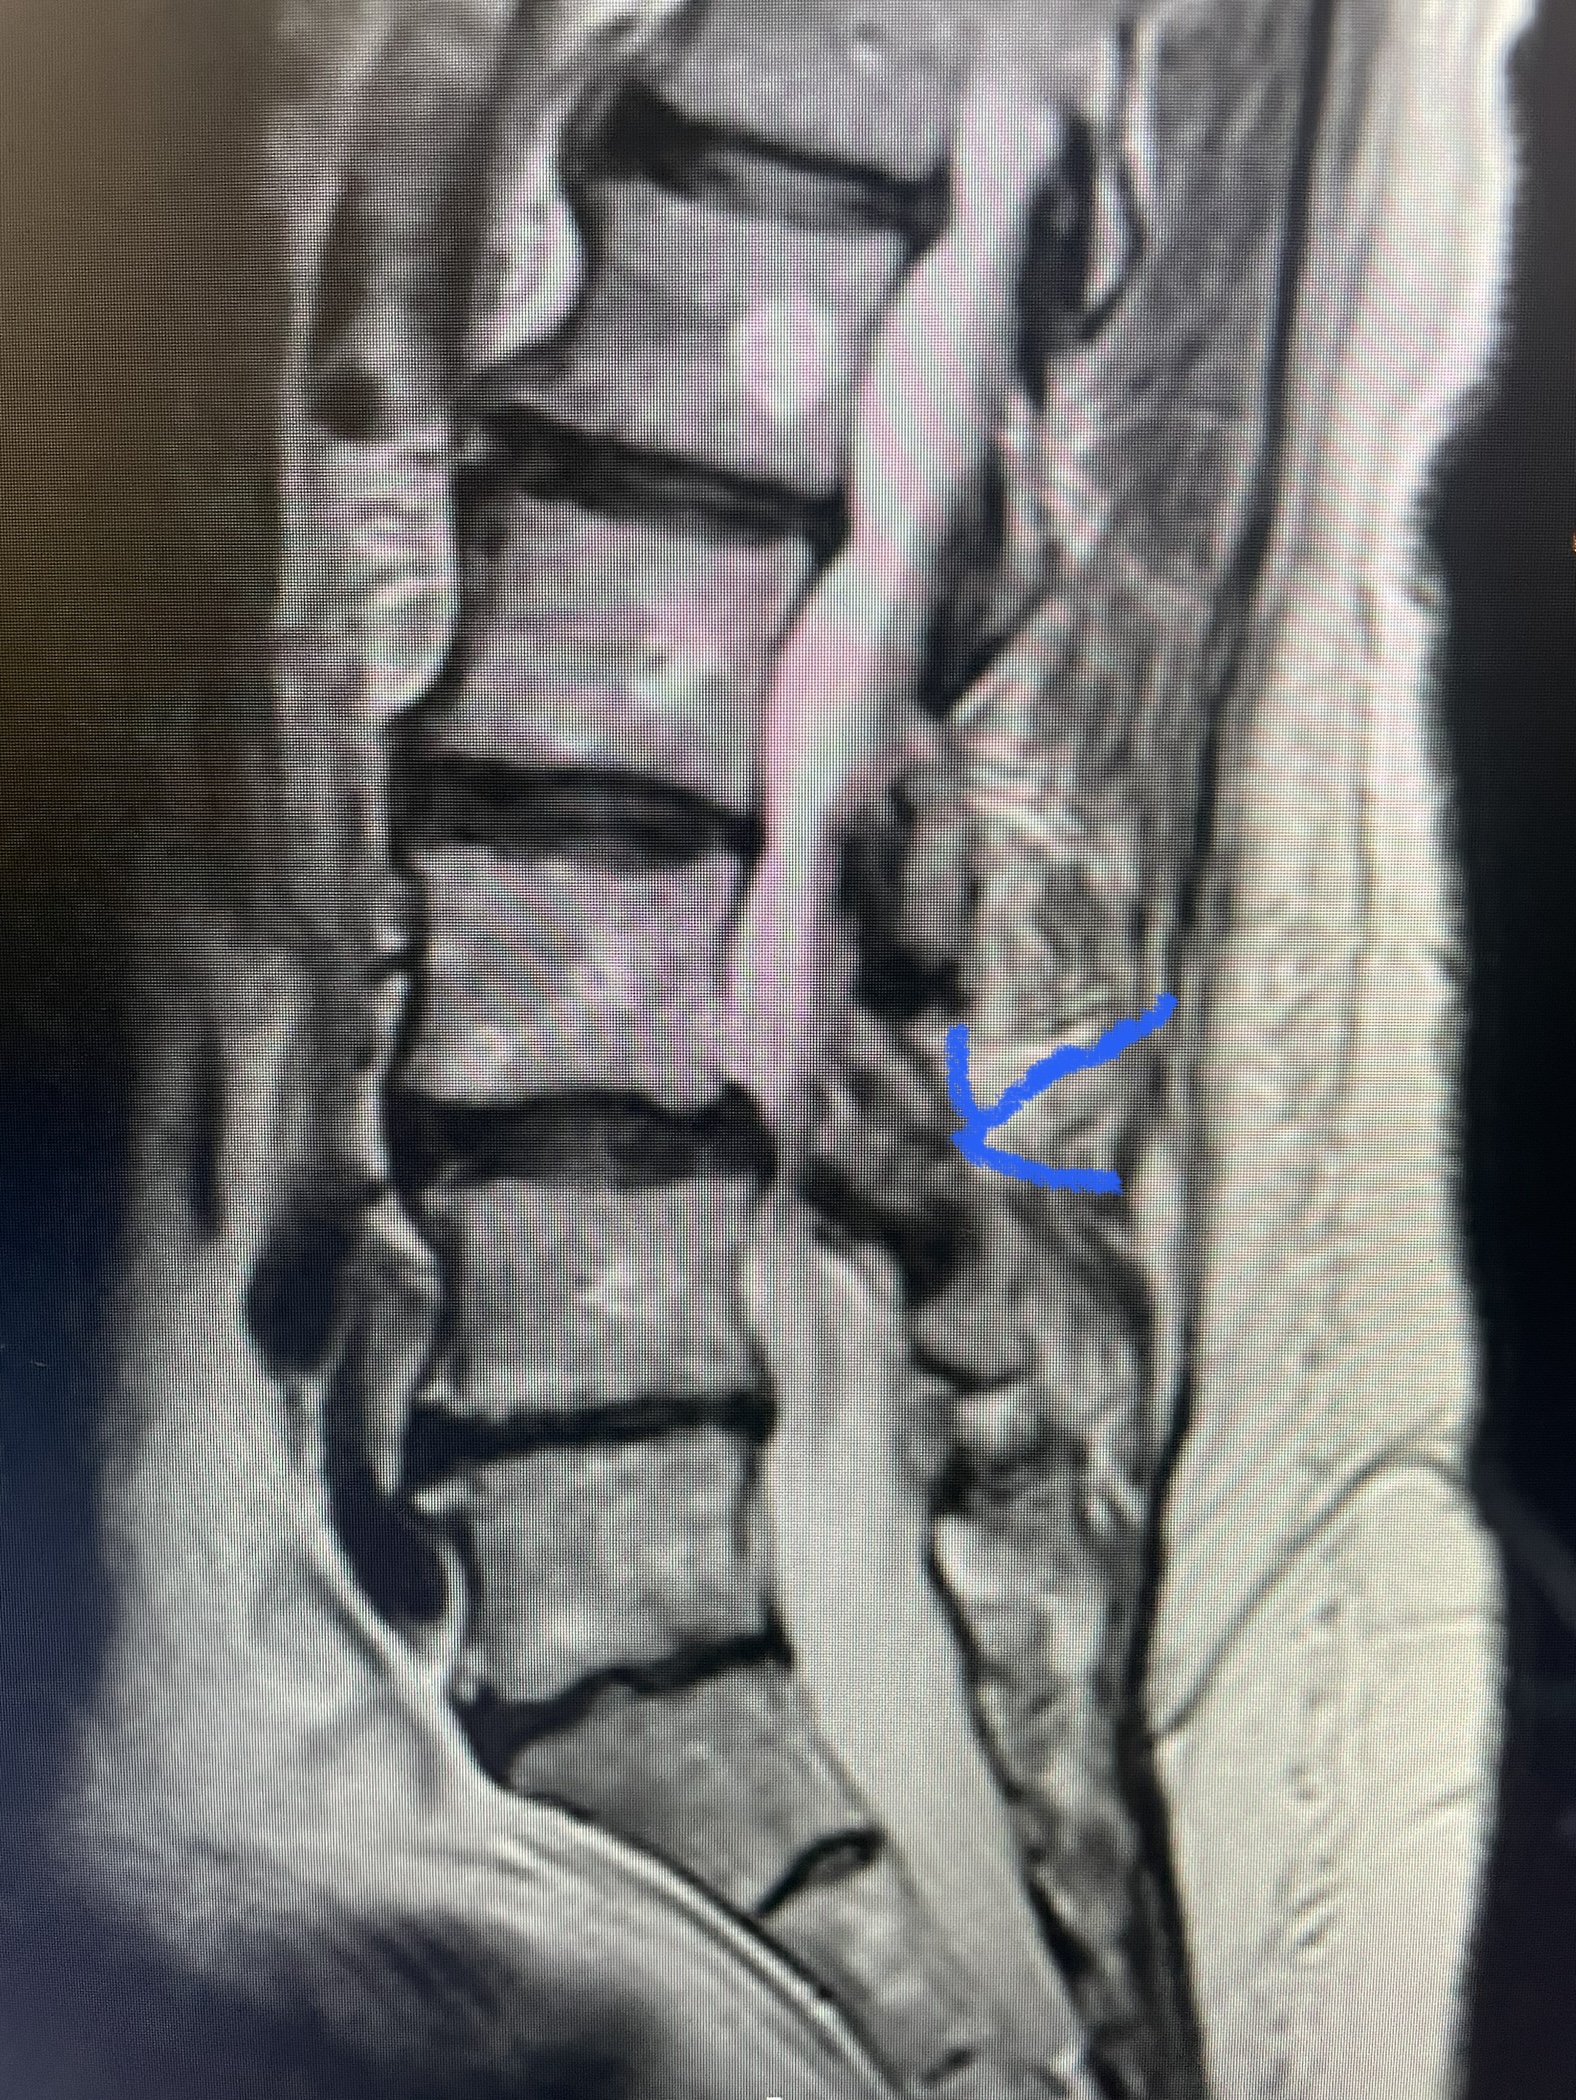

(Fig 1) Hydroxyapatite Coated Pedicle Screw

Pedicle screws can be coated with a thin layer of hydroxyapatite (Fig. 1), which is a natural form of calcium apatite present in human bone and plays a role in the structural strength of bone and in bone regeneration. By coating the screws with hydroxyapatite this can improve screw fixation or bonding at the bone-implant interface